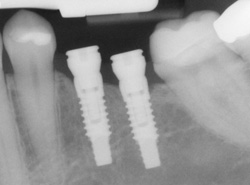

An implant is a synthetic tooth root in the shape of a post that is surgically placed into the jawbone. The “root” is usually made of titanium: the same material used in many replacement hips and knees, and a metal well suited to pairing with human bone.

Single or Multiple Implants

Implants are versatile. If you are missing only one tooth, one implant plus one replacement tooth will do the trick. If you are missing several teeth in a row, a few strategically placed implants can support a permanent bridge (a set of replacement teeth).

If you have lost all your teeth, a full bridge or full denture can be permanently fixed in your mouth with a strategic number of implants.